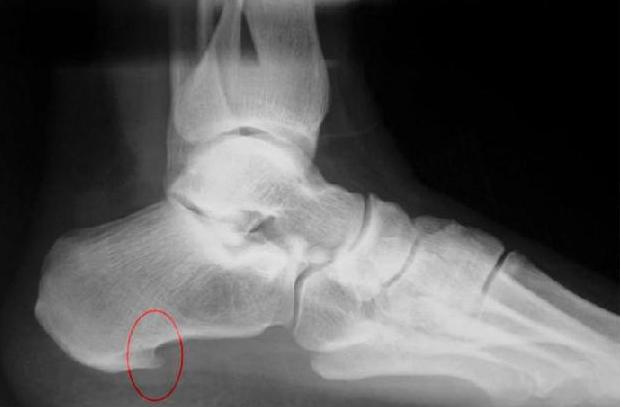

На фото фасциит

Для постановки диагноза обычно врачу достаточно выслушать жалобы пациента, провести осмотр и сделать рентген пораженной области. На рентгене определяется пяточная шпора, являющаяся костным наростом.

Если такового нет на снимке, то требуется дополнительно провести дифференциальную диагностику для исключения системных заболеваний вроде ревматоидного артрита, синдрома рейтера и других подобных состояний.

Плантарный фасциит на рентгеновском снимке